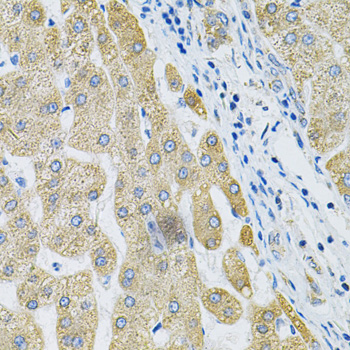

Immunohistochemistry of paraffin-embedded human liver cancer using ALG2 Antibody. |